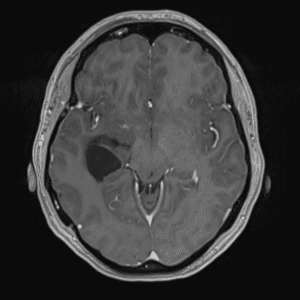

Brain Tumor Practice Cases

Case #3

Ganglioglioma